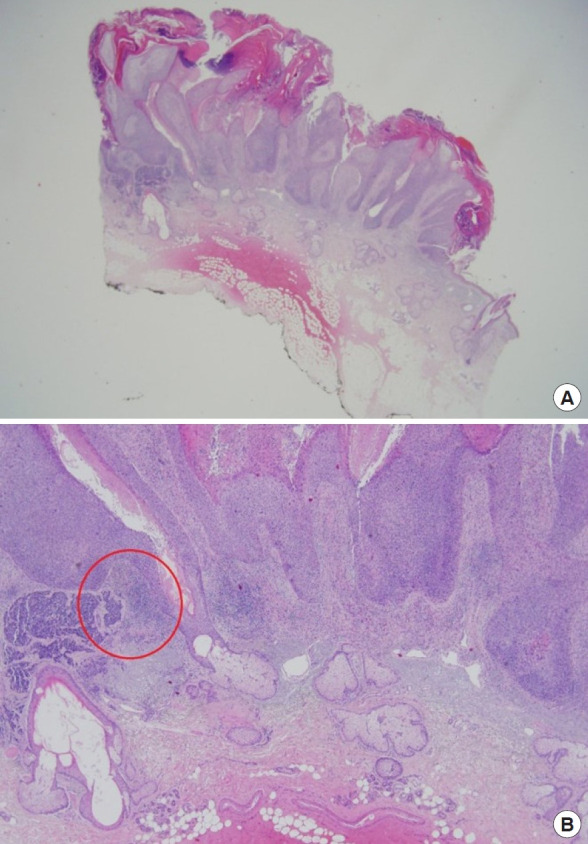

神经内分泌癌(NEC)是一种罕见的侵袭性皮肤肿瘤,具有内分泌和神经特征的共同表型。其表现为进展迅速,常见局部复发,常转移到局部淋巴结,偶尔累及全身。NEC的危险因素与其他皮肤癌相似,主要包括紫外线照射、年龄较大、t细胞免疫抑制、皮肤白皙和男性。NEC在免疫抑制人群中更为常见,我们报告一例罕见的NEC合并鳞状细胞癌(SCC)的肾移植患者。66岁男性,左脸颊有棕色斑块,穿刺活检提示原位SCC。大面积切除,缺损用双叶瓣重建。最终活检证实SCC合并神经内分泌分化癌,正电子发射断层扫描-计算机断层扫描证实无淋巴结转移或全身累及。患者无复发或其他术后并发症。

Neuroendocrine carcinoma (NEC) is a rare aggressive tumor of the skin with a shared phenotype of both endocrine and neuronal features. Its behavior includes rapid progression, common local recurrence, frequent metastasis to local lymph nodes, and occasional systematic involvement. The risk factors for NEC are similar to those for other skin cancers and mainly include ultraviolet light exposure, older age, T-cell immunosuppression, fair skin, and male sex. NEC is seen more frequently in the immunosuppressed population, and we report a rare case of NEC combined with squamous cell carcinoma (SCC) in a patient who underwent kidney transplantation. A 66-year-old man was referred with a brownish plaque on left cheek, and a punch biopsy result indicated SCC in situ. Wide excision was performed, and the defect was reconstructed using a bilobed flap. The final biopsy confirmed SCC combined with carcinoma with neuroendocrine differentiation, and positron emission tomography-computed tomography confirmed the absence of lymph node metastasis or systemic involvement. The patient showed no evidence of recurrence or other postoperative complications.